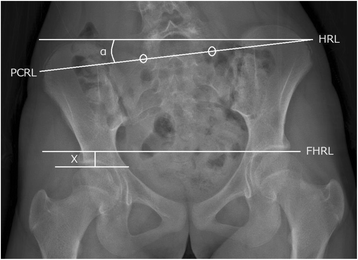

Fig. 2

Functional leg length discrepancy and pelvic obliquity assessed using two-dimensional standing radiograph. Functional leg length discrepancy (X) and pelvic obliquity (α) measured using the two-dimensional posterior-anterior standing radiograph obtained from the EOS imaging system. FHRL femoral horizontal reference line, HRL horizontal reference line, PCRL pelvic coronal reference line